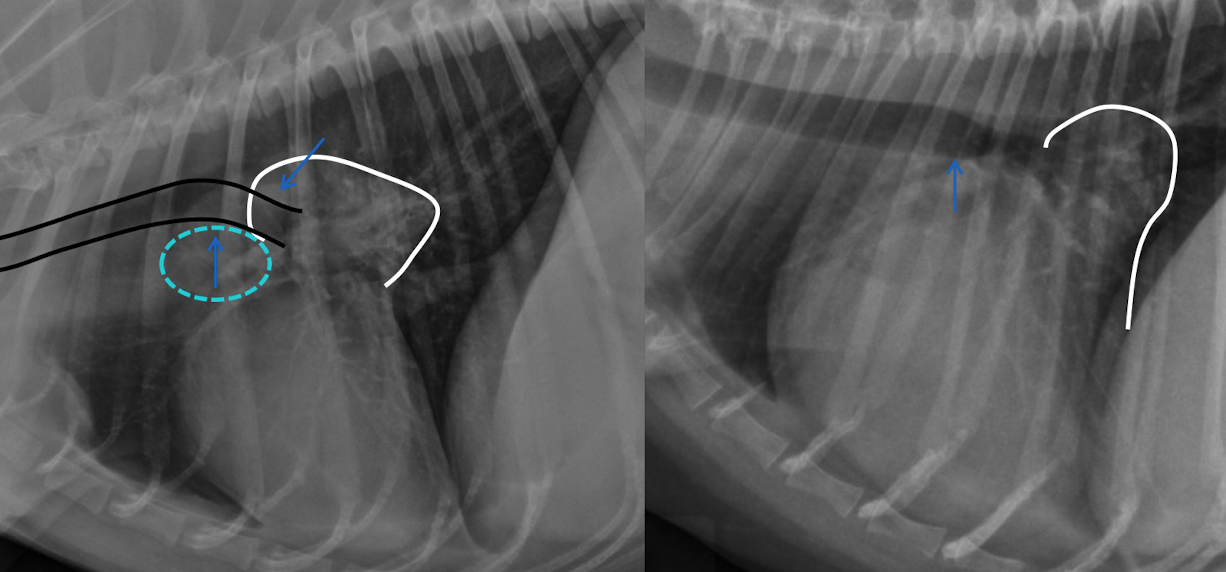

what is this showing

A

left: enlargment of middle tracheobronchial Lymph node → ventral displacement of carina

right: left atrial enlargmentdorsal displacement of carina

both will show bowing of the mainstem bronchi on VD (cowboy) and double opacity sign